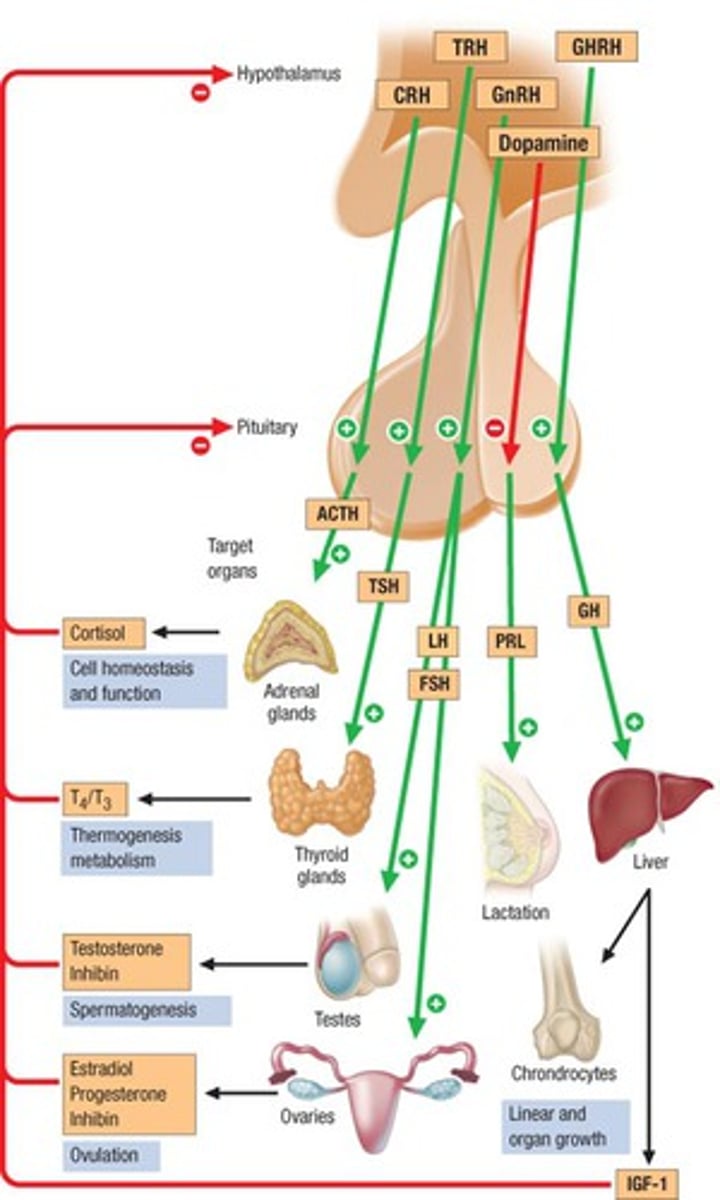

hypothalumus

small area near the base of the brain that is above the pituitary gland

pituitary gland

gland at the base of the brain that dangles under the hypothalamus

Adrenal Glands

a pair of endocrine glands that sit just above the kidneys

hypothalamus hormones

ADH, oxytocin, regulatory hormones

pituitary gland hormones

LH, FSH, GH, TSH, ACTH, Prolactin, Oxytocin, ADH

adrenal glands hormones

Epinephrine, norepinephrine, glucocorticoids- cortisol, mineralocorticoids- Aldosterone